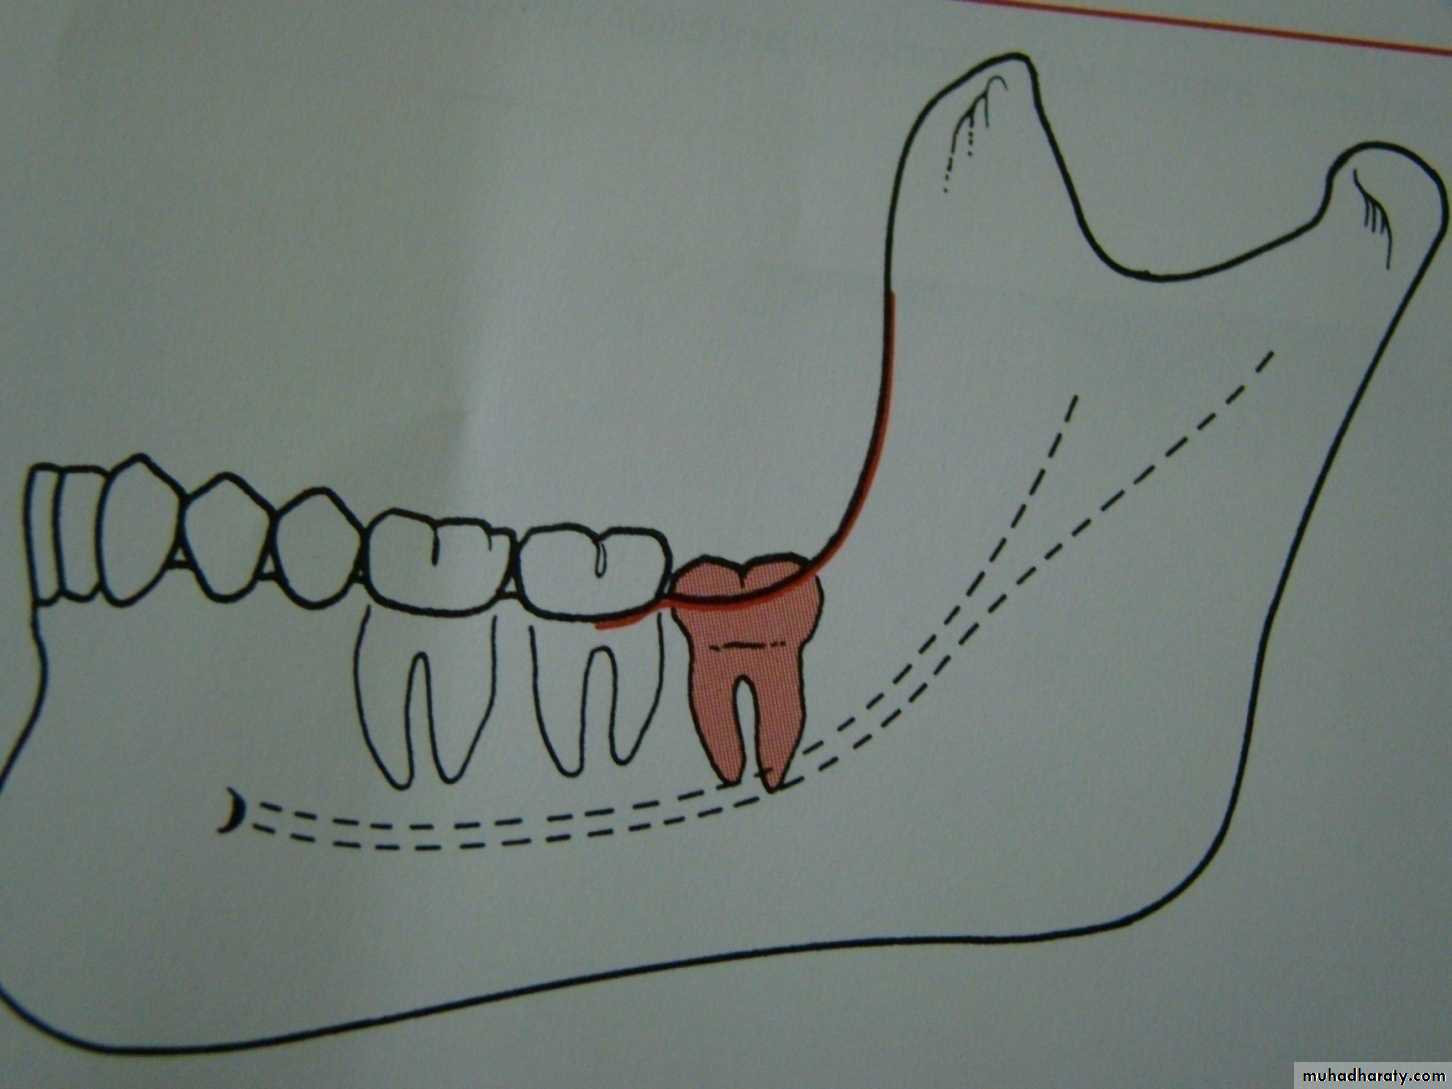

Winters classification of impacted lower third molar

mesioangular

hotizontalvertical

distoangular

Winter’s lines

1-White line: it is an imaginary line draw along the occlusal surface of erupted first and second molars extend posteriorly over 3rd molar region . Its benefit is to determine the angulations of an impacted tooth and its relationship with occlusal surface of erupted 2nd molar(depth).2- Amber line: It is a line drawn from the surface of bone laying distally to the 8 and to the crest of interdental septum or alveolar septum between 6 and 7. it determine the amount of bone removal

3-Red line : it is draw perpendicular from amber line to an imaginary point of elevator application located mesially to the CEJ except in Disto angular impaction it is distally located . It is used to measure the depth of the impacted tooth.

Note: Any tooth with red line length more than (5 mm) it is better to remove it under G.A.